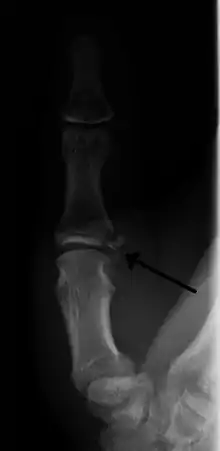

الكسر القلعي (بالإنجليزية: Avulsion fracture) هو كسر في العظام يحدث عند انفصال جزء من العظم بعيداً عن الكتلة الرئيسة من العظم نتيجة الصدمات الجسدية.[1][2][3] حيث يمكن أن يحدث هذا في الرباط بسبب القوى الخارجية للجسم (مثل السقوط أو الشد) أو في الوتر بسبب تقلص العضلات التي تفوق قوة ترابط العظام معاً. ويتم منع اقتلاع العضلات عموماً وذلك بسبب الاضطرابات العصبية في العضلات المنقبضة. ويمكن للمدربين الرياضيين ذوي القدرة العالية التغلب على تثبيط الجهاز العصبي للقوة وإنتاج قوة أكبر بكثير و قادرة على كسر أو تفتيت العظام.

إذا كان الكسر بسيط، فإن أخذ قسطاً من الراحة واستخدام الضمادة عادة ما يكون كافياً، ولكن في الحالات الأكثر خطورة قد تكون الجراحة ضرورية. و من الممكن استخدام الثلج للتخفيف من التورم/الانتفاخ. بالنسبة للكسور القلعية المنزاحة من مكانها فإن أفضل طريقة للتعامل معها عن طريق إما الرد المفتوح و التثبيت الداخلي أو الرد المغلق و التدبيس. و يستخدم الرد المفتوح (باستخدام الشق الجراحي) والتثبيت الداخلي عند الحاجة بدبابيس أو مسامير أو أدوات مماثلة لعلاج الشظية العظمية.